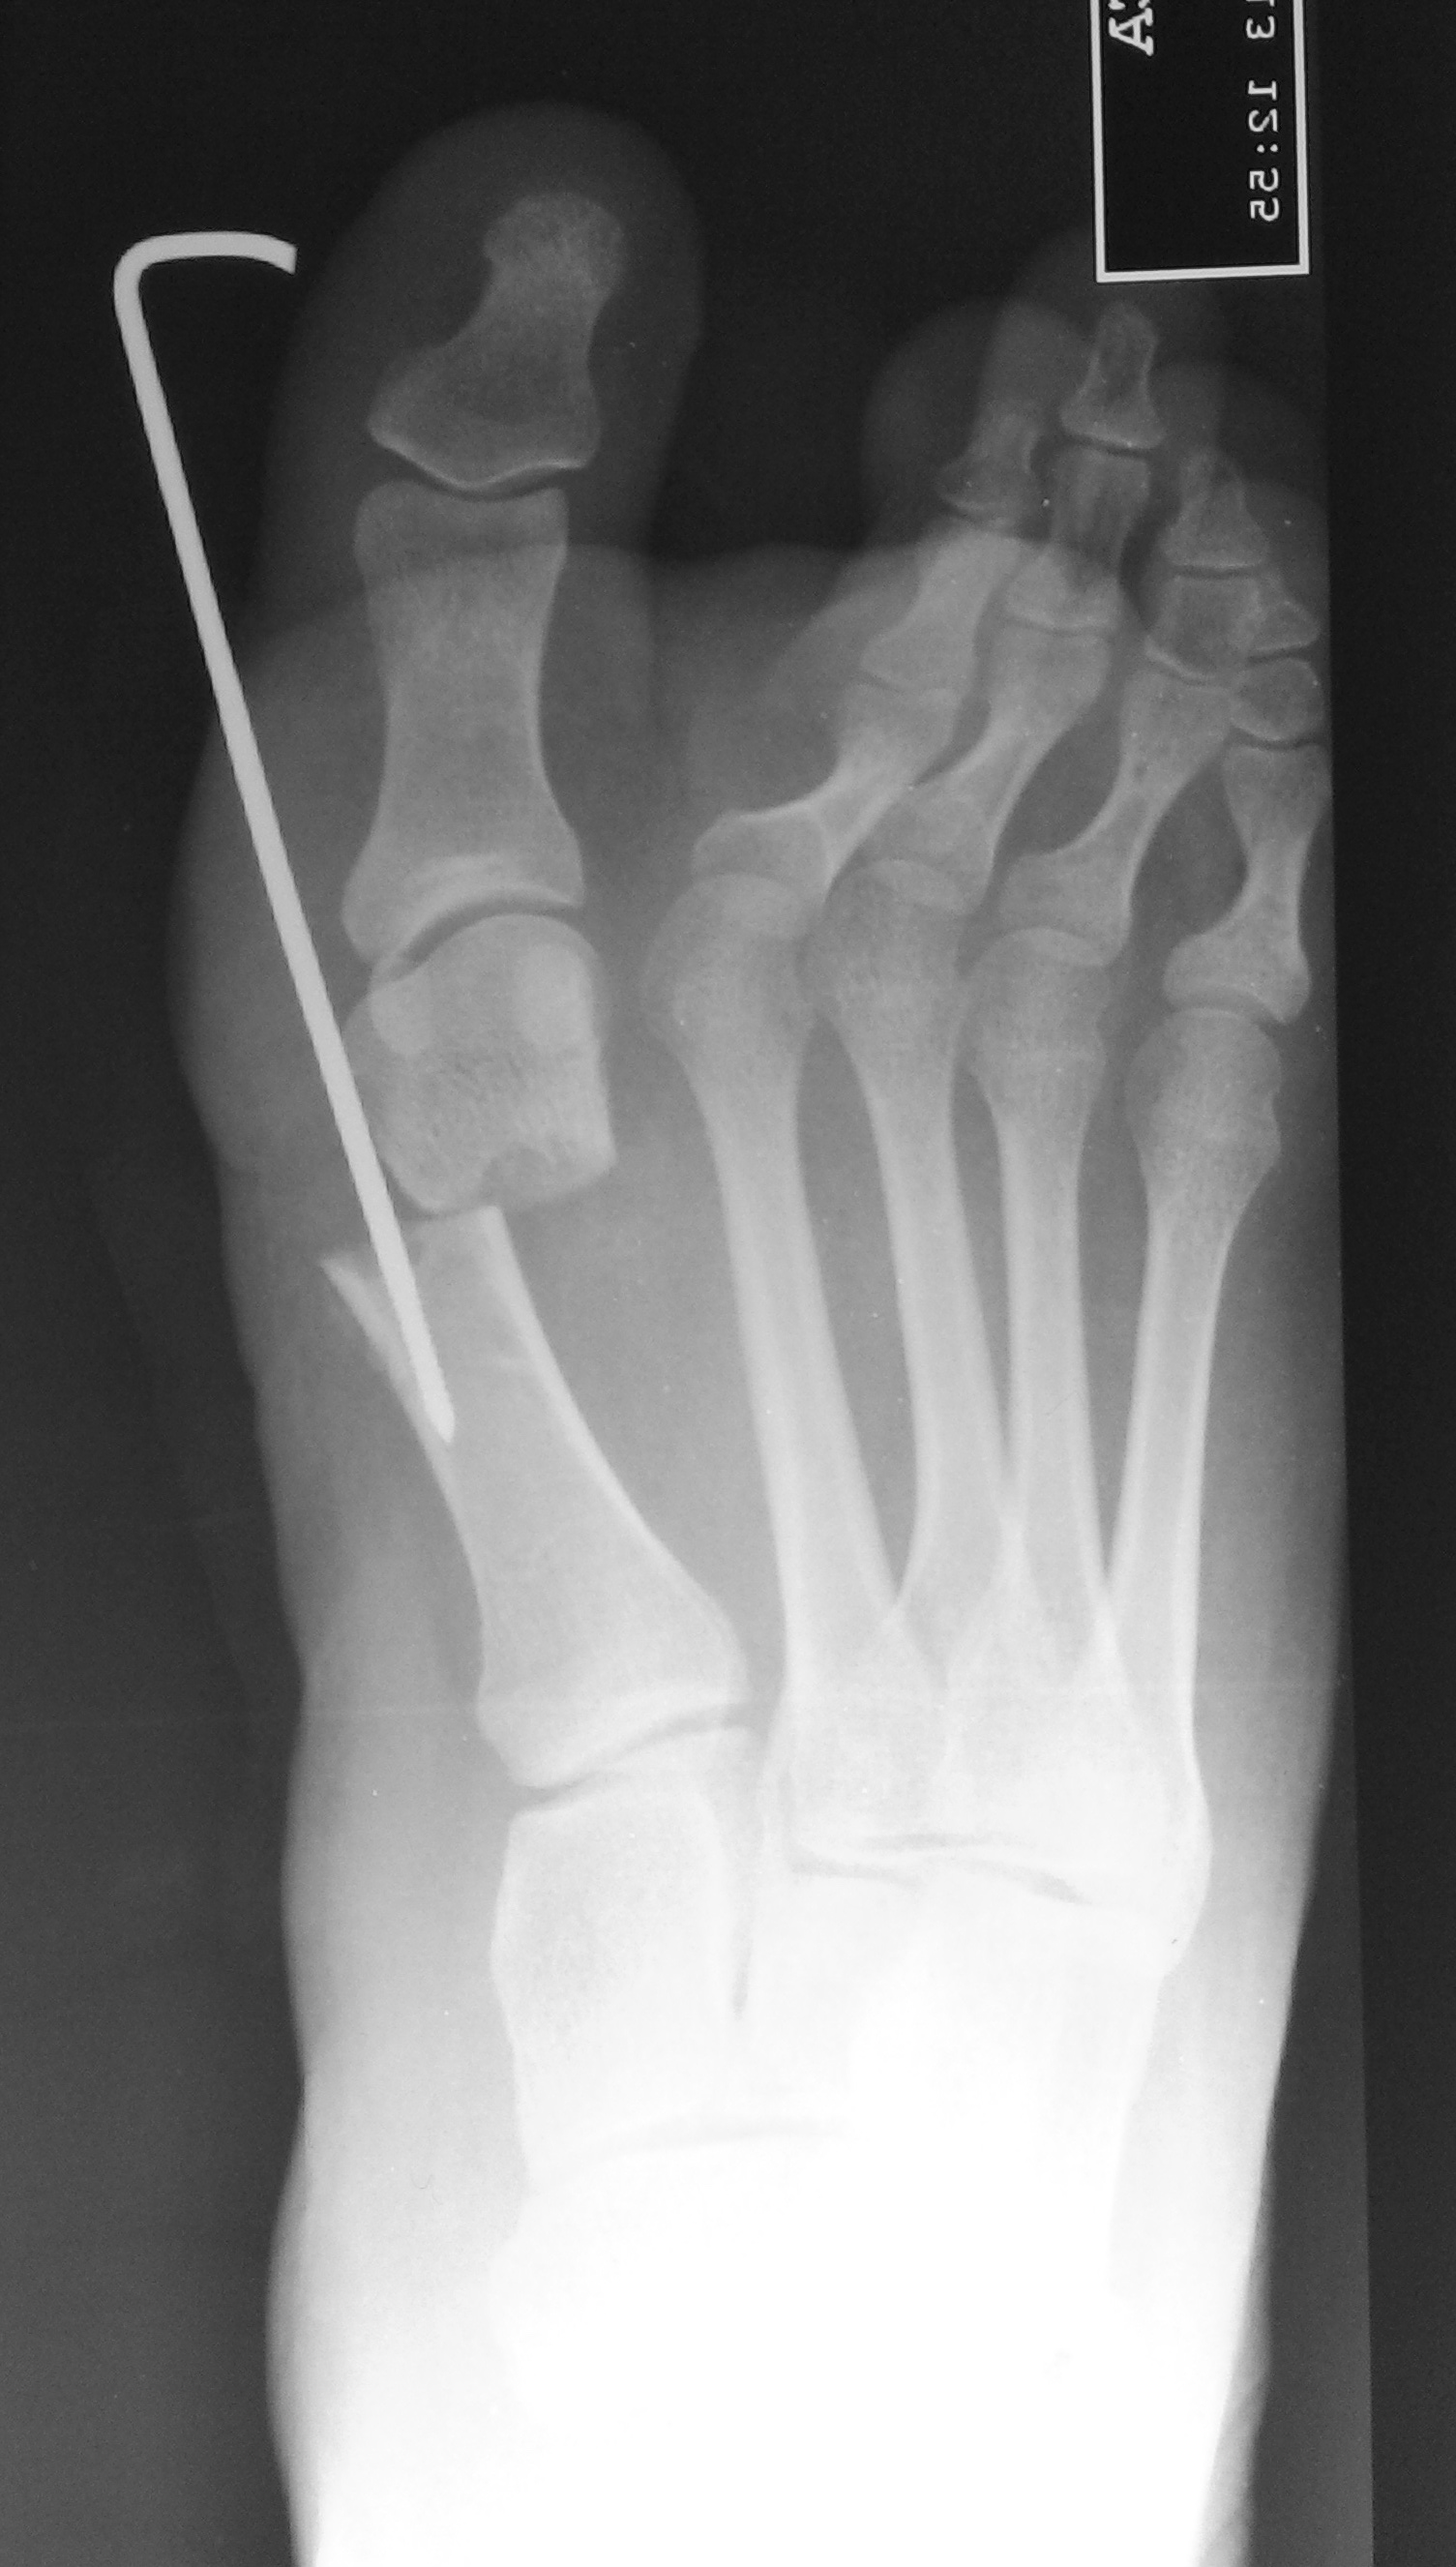

IntroducciónEl Hallux valgus es una deformidad frecuente de la articulación metatarso falángica del primer rayo que predomina en el sexo femenino. En la actualidad hay más de cien técnicas descriptas y popularizadas para el tratamiento de esta patología. El tratamiento quirúrgico del hallux valgus en forma percutánea es un procedimiento demandante que implica una curva de aprendizaje prolongada y que constituye un desafío para el cirujano especialista.Material y MétodosEstudio de cohorte retrospectivo. 70 pacientes operadas de hallux valgus con tecnica percutanea de Bosch. Se evaluaron características del intraoperatorio y hospitalización, resultados funcionales de acuerdo a score AOFAS y molestias con la utilizacion de clavija para fijacion de osteotomia; y resultados radiológicos El seguimiento promedio fue de 12,8.ResultadosEl tiempo promedio de utilización de clavija fue de 31,44 días, rango entre 7 y 45 días. 18 pacientes presentaron insatisfacción o incomodidad con la utilización de la clavija en el PO pero manifestaron que se volverían a operar con una técnica quirúrgica similar. Sin embargo, 3 pacientes que presentaron conformidad con la utilización de la clavija en el PO, manifestaron que no volverían a operarse con esta técnica. Todos los pacientes presentaron remisión completa del dolor con un resultado AOFAS final de 96,21 puntos.DiscusiónLa osteotomía metatarsiana percutánea ha superado los objetivos en el tratamiento de la cirugía de hallux valgus, obteniendo similares resultados clínico - radiográficos que las técnicas abiertas convencionales, pero disminuyendo los daños sobre las partes blandas. La crítica hacia la cirugía de Bosch es el riesgo de rigidez post operatoria pero, ya que se trata de una osteotomía extra articular, este riesgo queda minimizadoConclusiónLos resultados de este estudio demuestran que la cirugía de Bosch y la estabilización de la osteotomía con una clavija de Kirschner, es una solución eficaz para el tratamiento del hallux valgus.Descargas